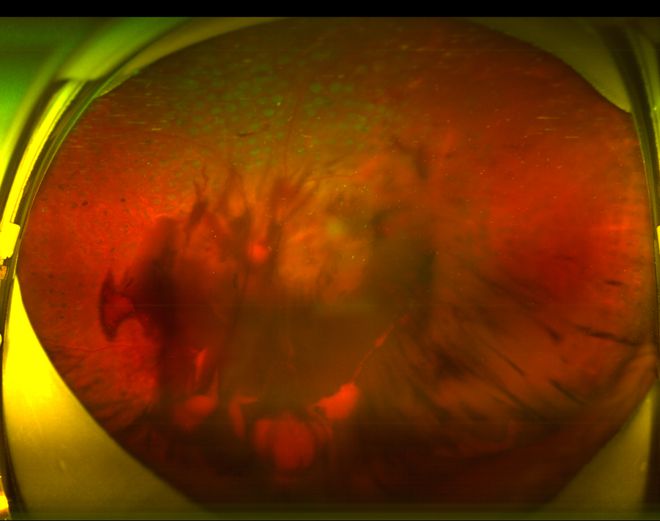

经检查,医生发现患者的双眼眼底存在大量出血点及新生血管,而左眼因玻璃体出血导致视网膜被遮挡,因此才会出现眼前黑影的情况,这些都是糖尿病性视网膜病变的症状。经过进一步询问得知,小刘在三年前就被诊断出患有糖尿病,期间还出现过手脚麻木的症状,但一直因不重视而未接受正规治疗。此外,他还偏好用含糖饮料代替水来解渴,饮食习惯也偏向高热量和辛辣食物,致使其糖化血红蛋白水平高达8.5%。

面对如此严峻的情况,门诊医生告知患者双眼眼底随时可能出现因严重出血而出现失明的风险,并立即为他安排紧急处理措施:包括双眼注射药物以抑制新生血管生长以及全视网膜光凝术,旨在阻止病情的进一步恶化。不幸的是,由于情况过于严重,小刘的左眼还是发生了严重的内出血,从原本的0.4的视力急剧下降至仅能看清50厘米内的物体。随后,医生们为他实施了玻璃体切除手术,成功清除了眼内的积血,使左眼恢复了一定程度的视力。

糖尿病视网膜病变

糖尿病眼底出血